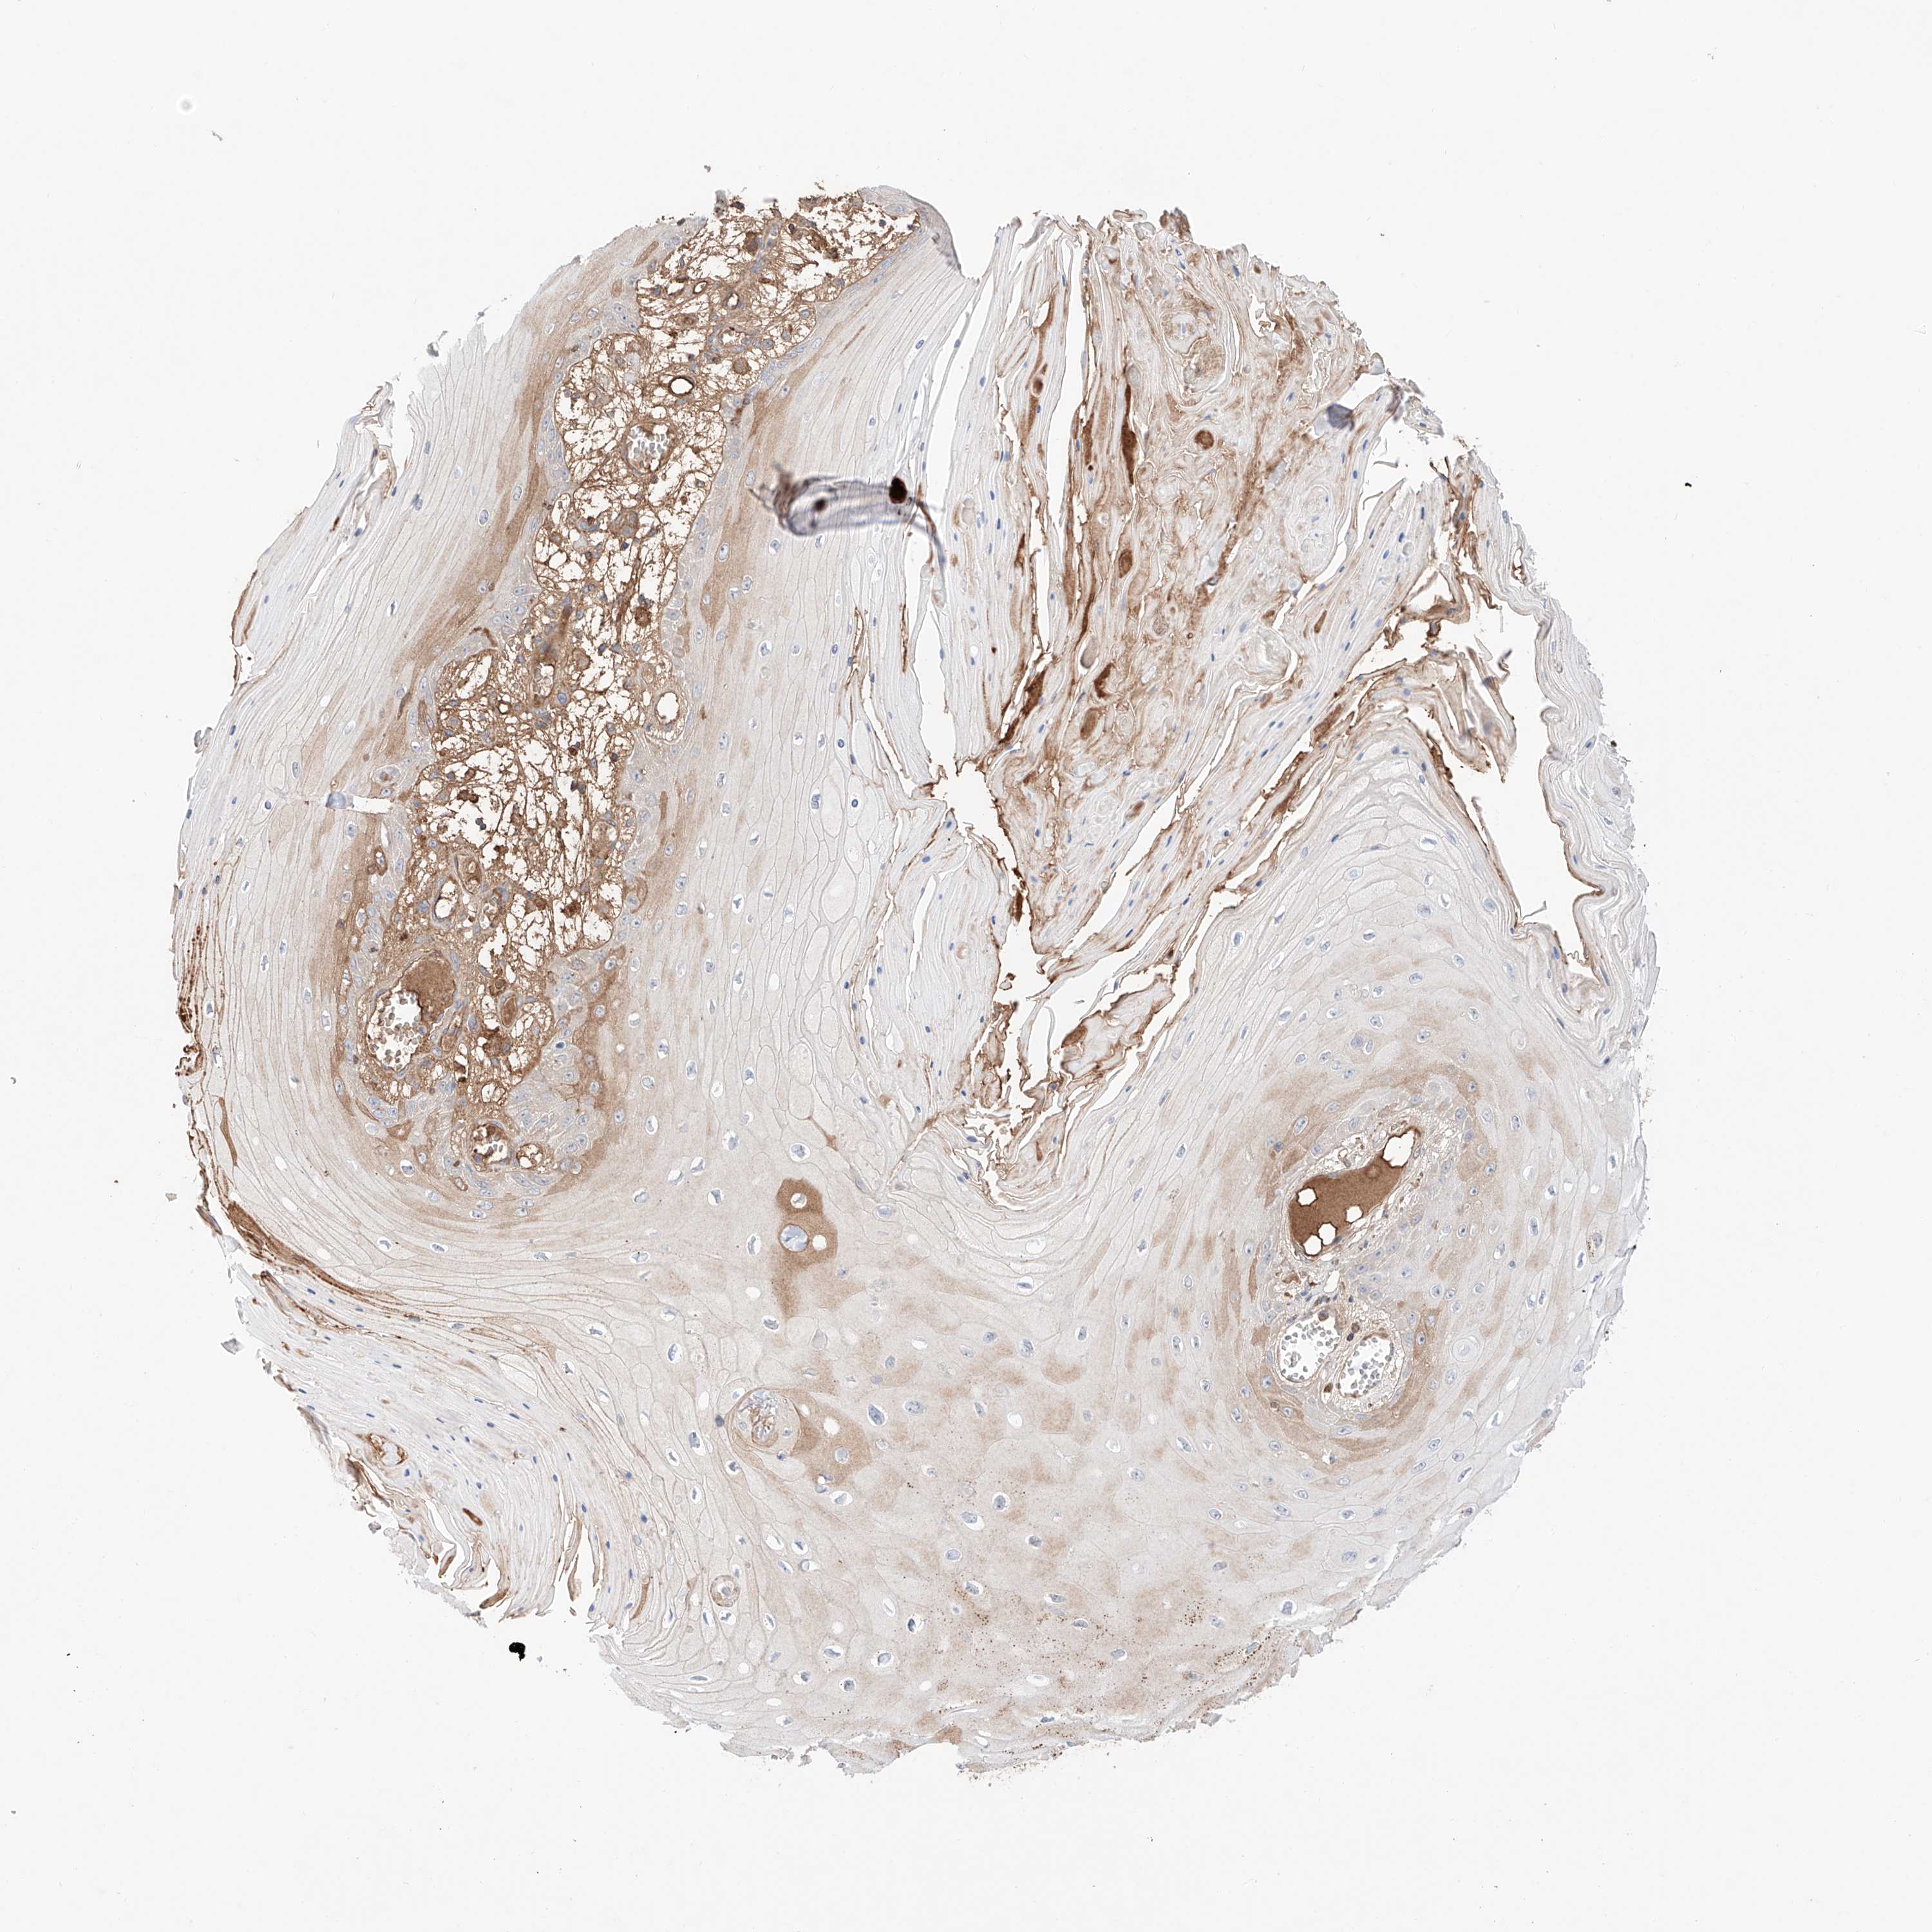

Basal cell and squamous cell cancer

SKIN CANCER - Protein expressioni

A mouse-over function shows sample information and annotation data. Click on an image to view it in a full screen mode. Samples can be filtered based on level of antibody staining by selecting one or several of the following categories: high, medium, low and not detected. The assay and annotation is described here.

Each image is clickable and will lead to virtual microscopy that enables deeper exploration of all samples and also displays staining intensity scores, fraction scores and subcellular localization as well as patient and tissue information for each sample.

Antibody HPA030646

Staining

High

Strong

>75%

Location

Nuclear

Basal cell carcinoma